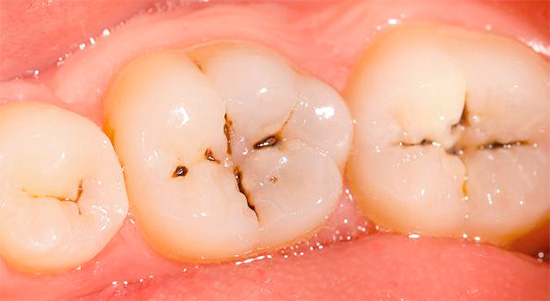

Un aspetto tipico dei denti con carie cronica è mostrato nella foto qui sotto:

Non ci sono lesioni estese dei denti e in alcuni punti le aree scure sono di dimensioni molto ridotte e spesso non attirano l'attenzione del paziente. Di solito il dolore è assente.

- La carie superficiale cronica porta alla formazione di una cavità nello smalto dei denti, ma senza danni alla dentina. Tale cavità non ha bordi sporgenti, è ampia, ben aperta, lo smalto stesso di solito si scurisce a causa della pigmentazione, ma mantiene una durezza relativamente elevata.

- La carie media cronica è caratterizzata da un'ampia cavità che colpisce la dentina. In questo corso, la cavità non ha ammorbidito la dentina, ma solo pigmentata dentina cariata. Il fondo è denso con lievi sporgenze e rugosità, che indica un processo lento nella fase di compensazione a causa della sostituzione della dentina.